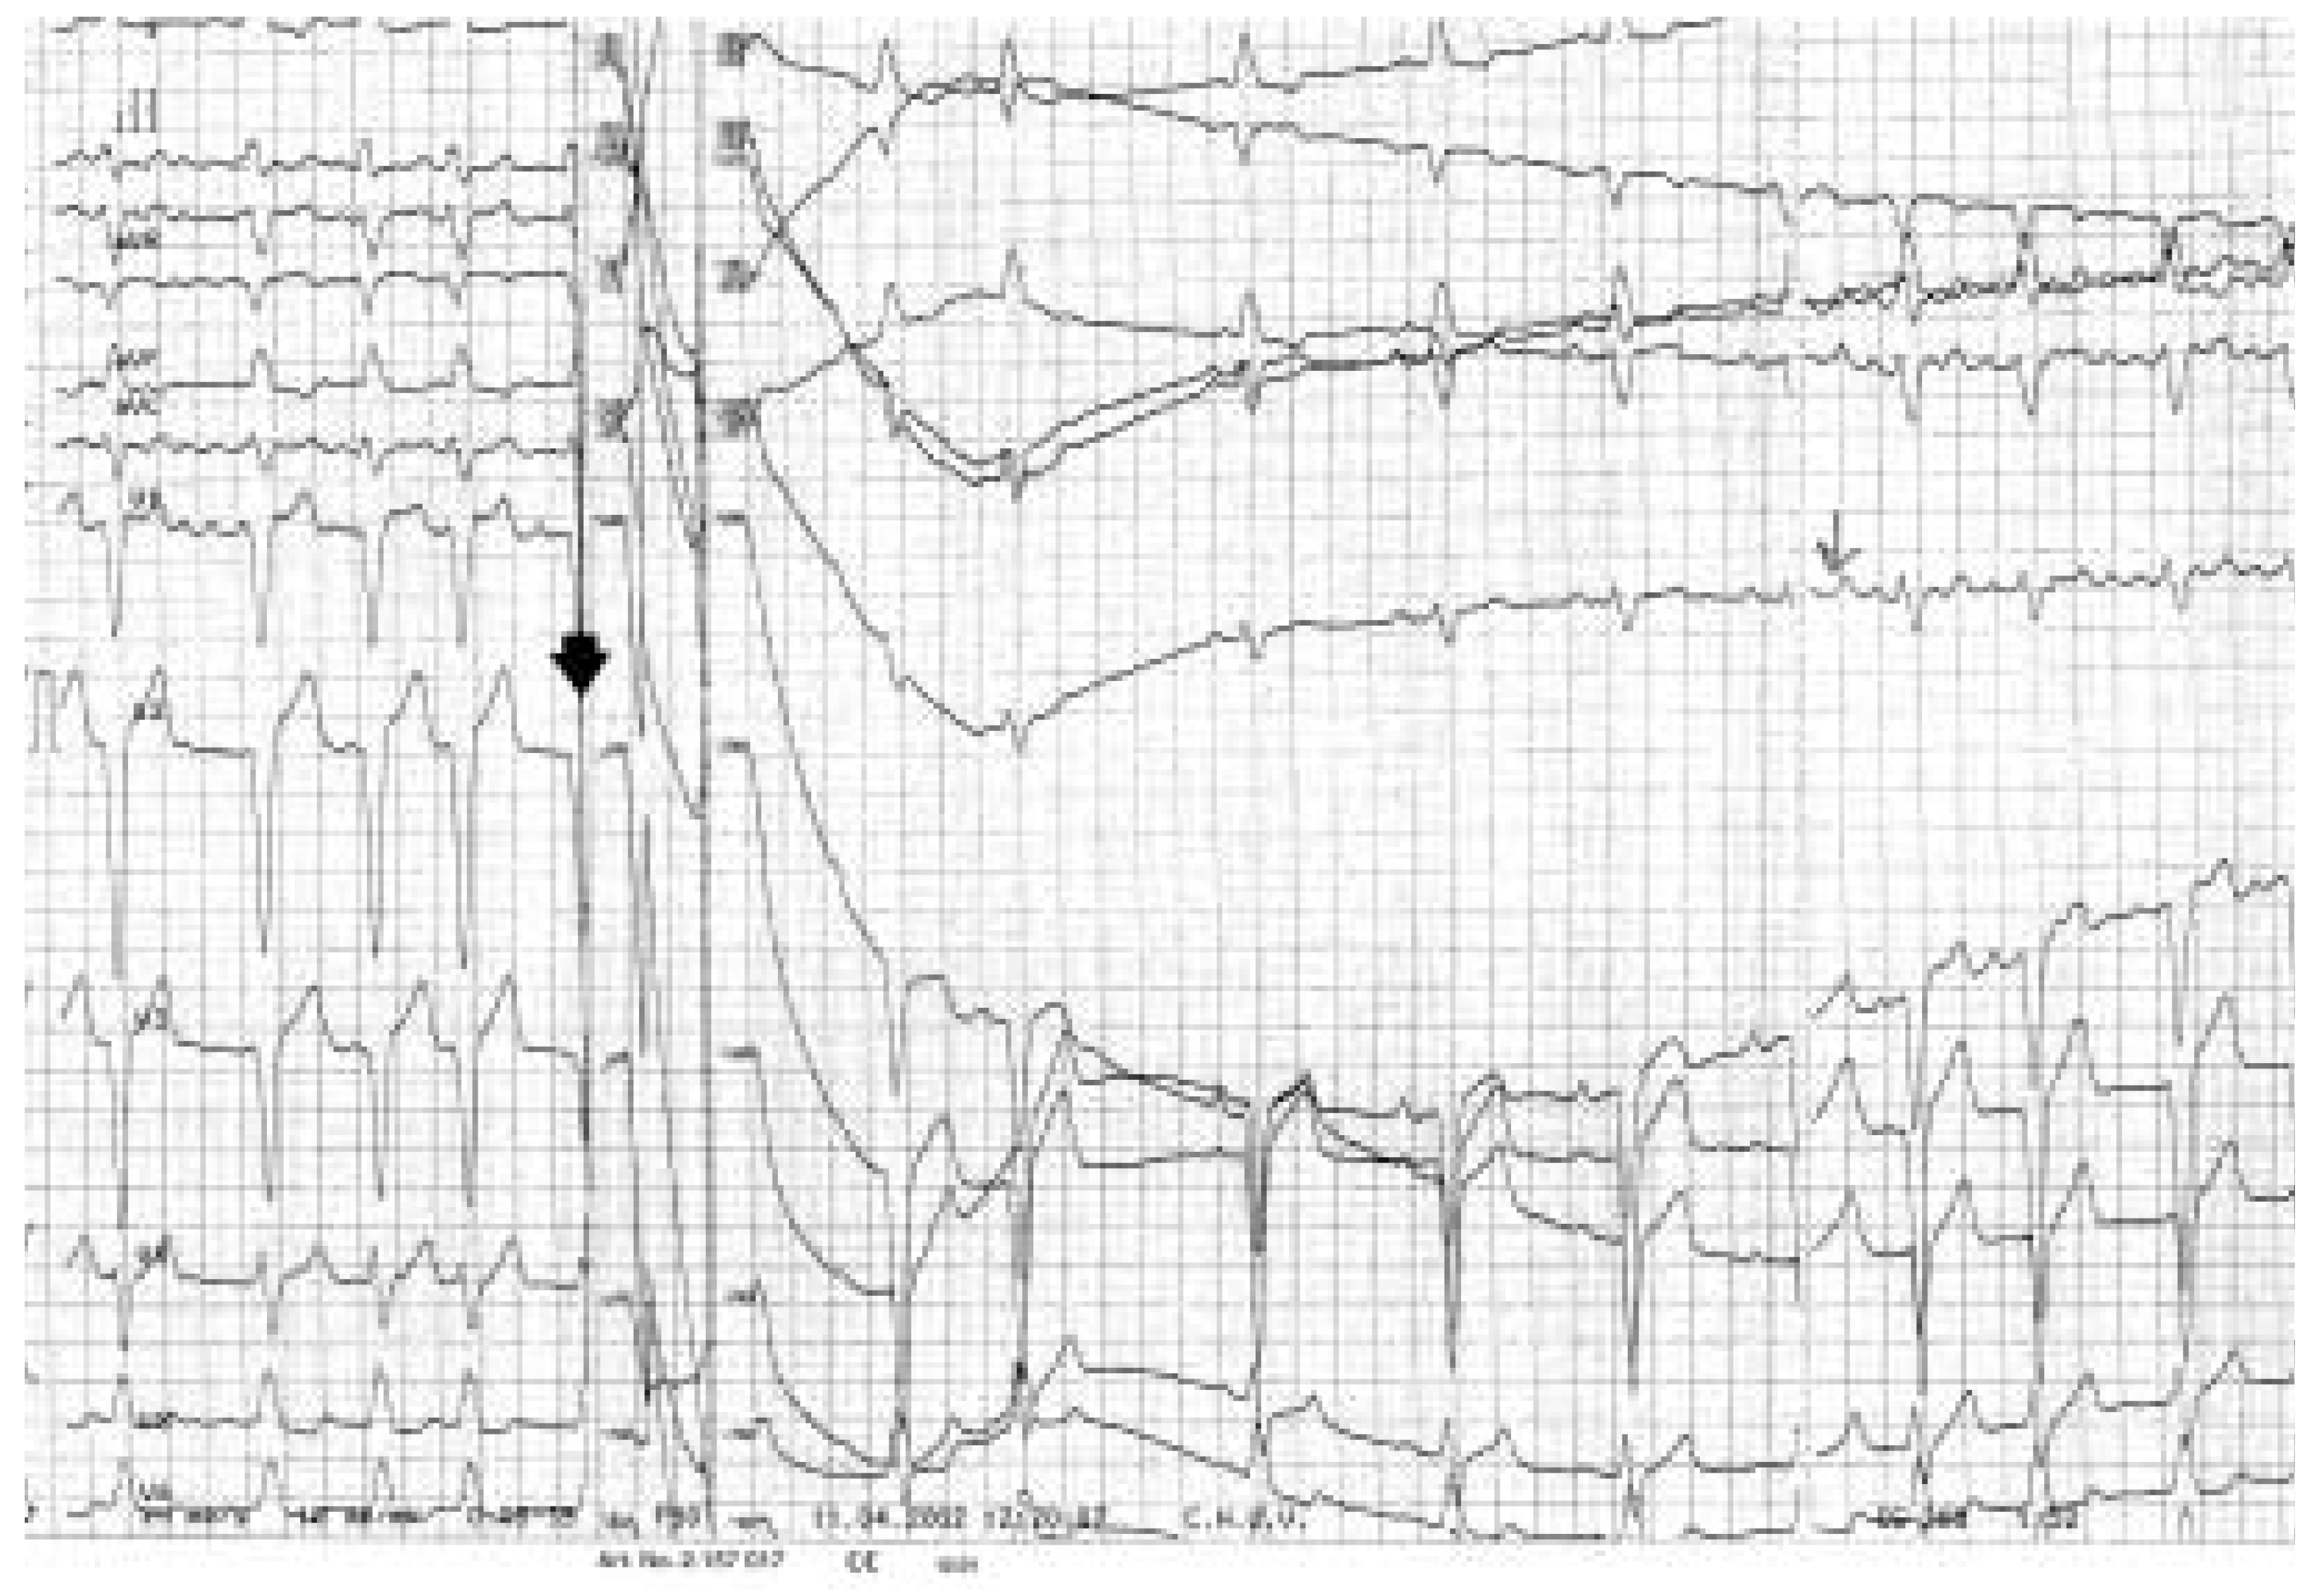

Fibrillation Auriculaire

Données cliniques